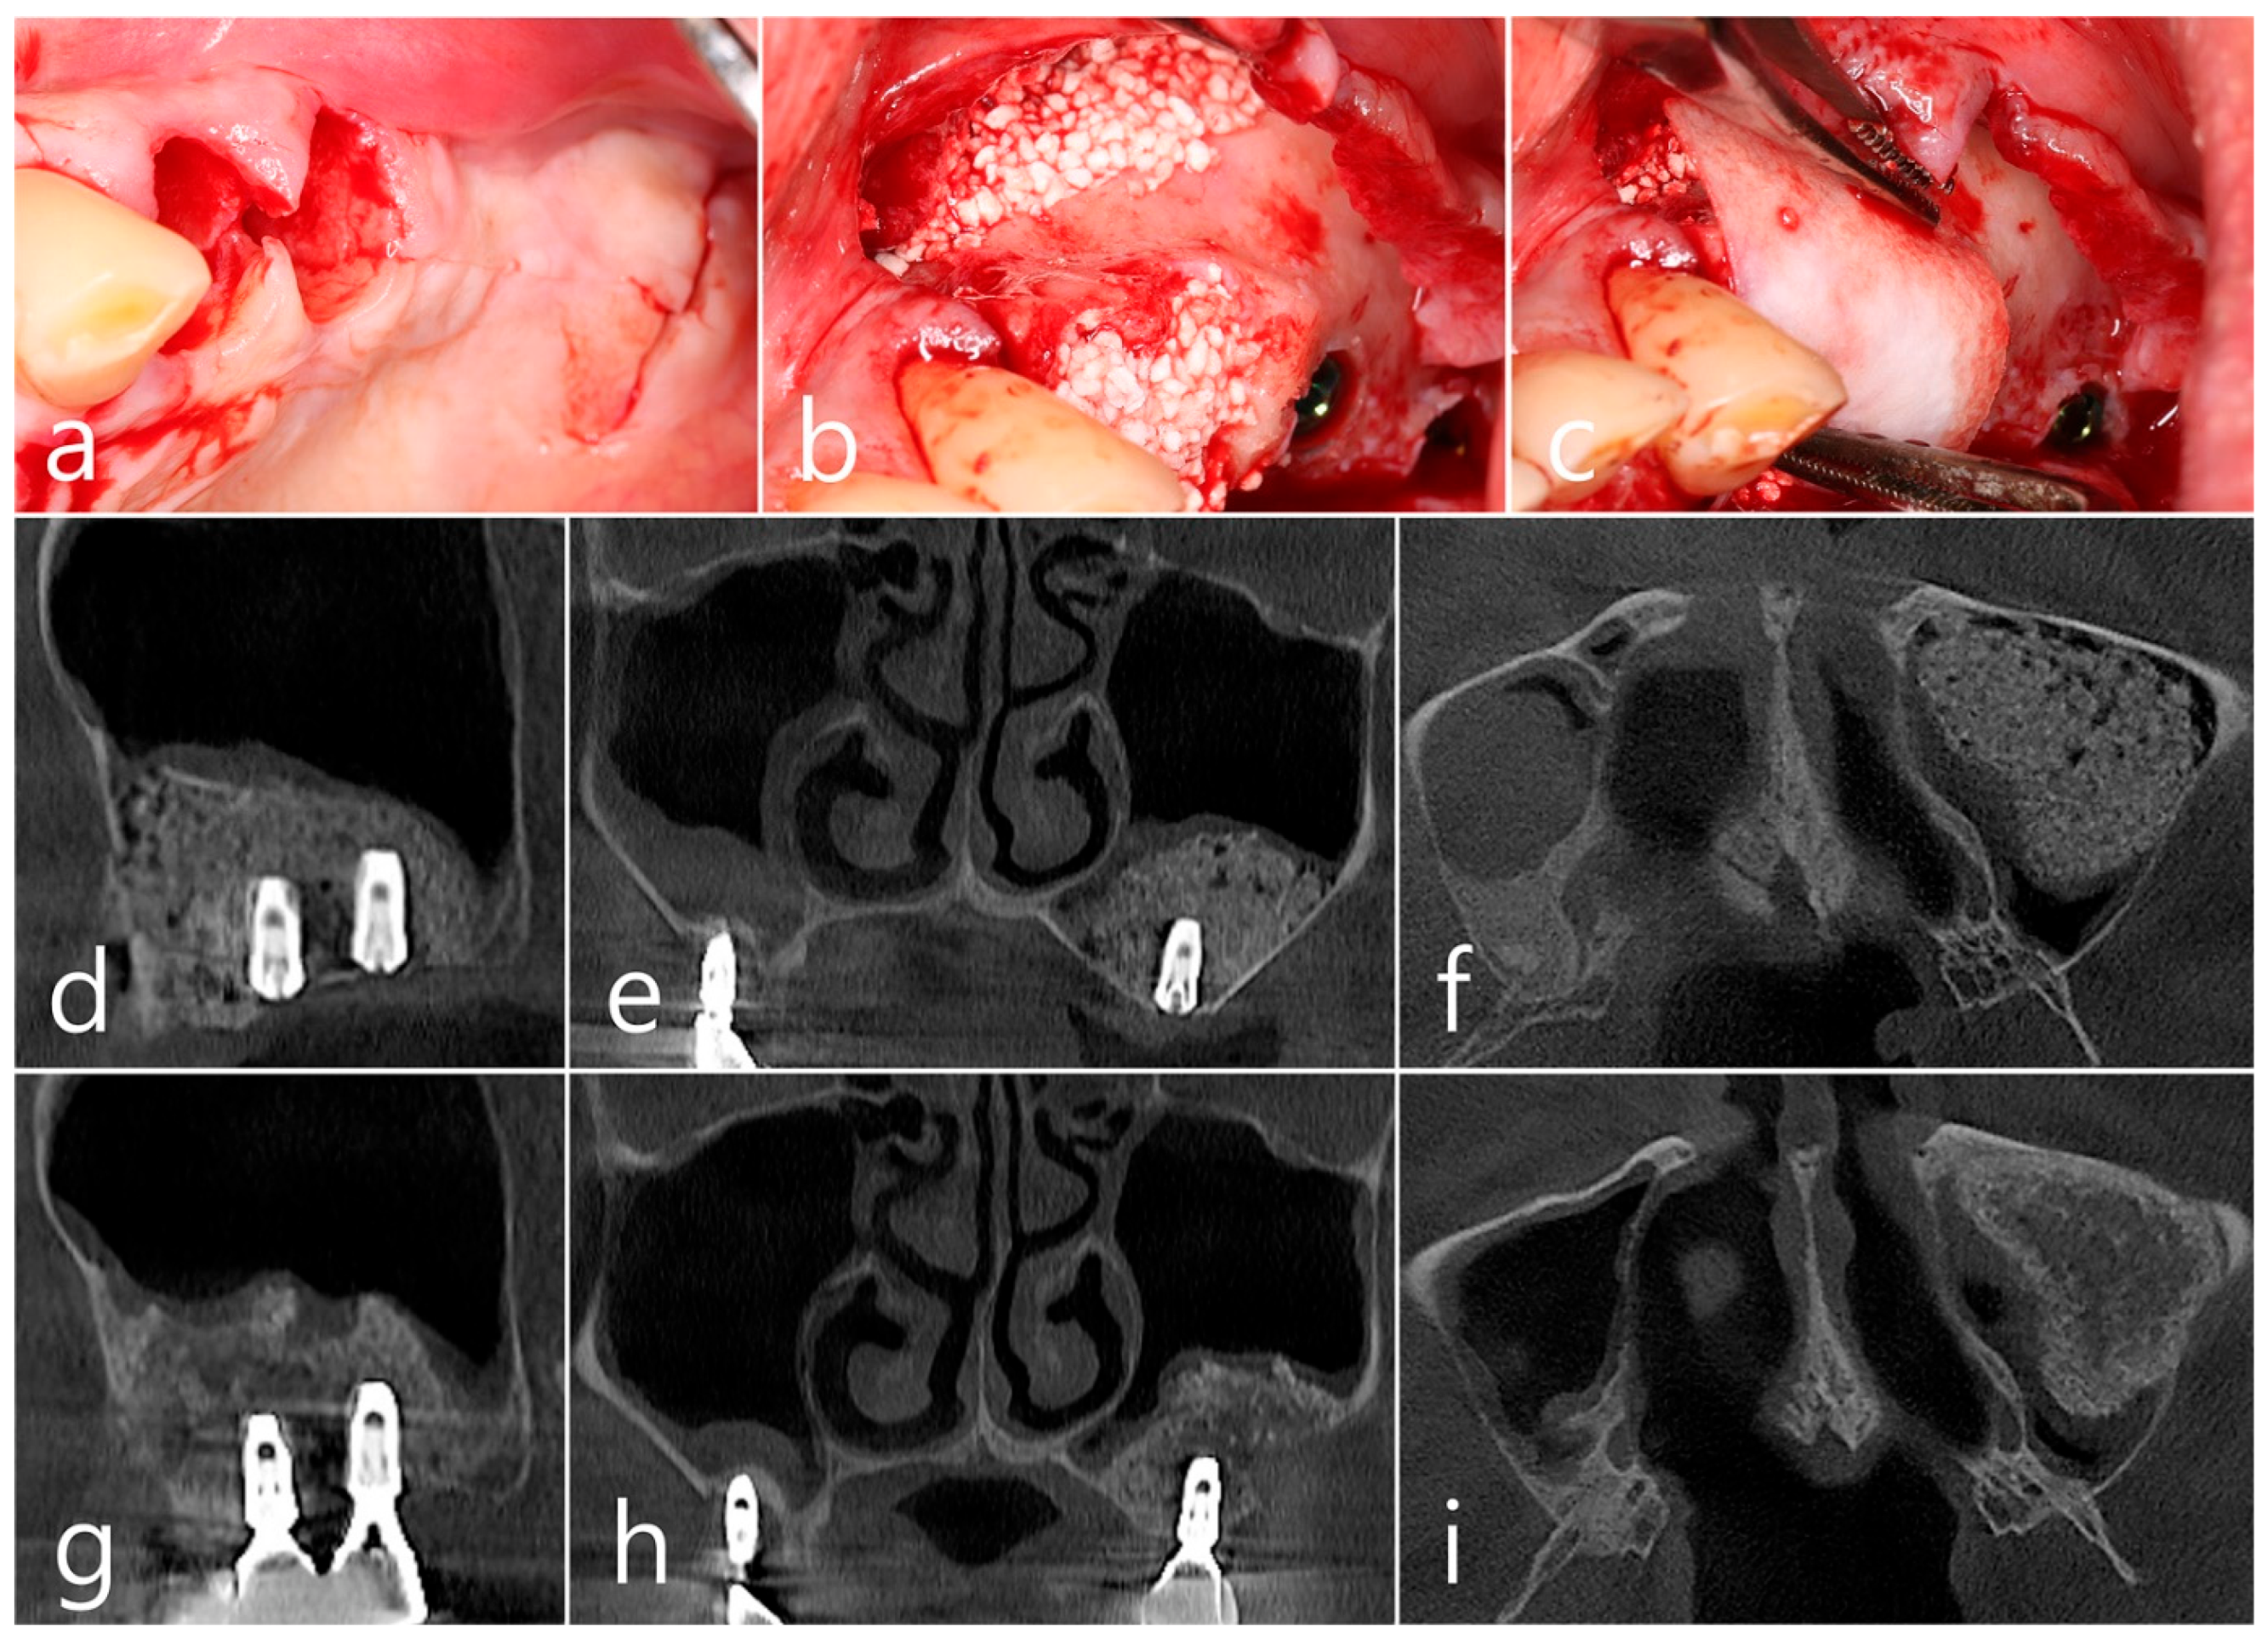

In the clinical findings 1 year after prosthesis delivery, there were no clinical signs such as edema or fistula (Figure 5a). Surgical intervention was decided according to the radiographic images. Under local anesthesia, the buccal mucoperiosteal flap was reflected. The peripheral bone of the #25 and #26 implant apexes was resorbed, and the implant surfaces were exposed. The facial bone of implant #26 was also absorbed, exposing the implant surface (Figure 5b). Inflammatory granulation tissue within the bone defect was thoroughly removed, and a titanium brush and curette were used to decontaminate the implant surface (Figure 5c). Additional detoxification was performed with tetracycline HCl on the exposed implant surface (Figure 5d). Thorough saline irrigation was performed (Figure 5e). The bone defect was filled with Osteon II (Genoss, Suwon, Republic of Korea) and covered with a resorbable collagen membrane (Genoss, Suwon, Republic of Korea) (Figure 5f). The mucoperiosteal flap was closed with 4-0 nylon (Figure 5g). The specimen was fixed in 10% formalin for histopathological examination. Necrotic bone and bone graft particles were scattered throughout the specimen, and inflammatory cell infiltration was also seen. However, no pseudostratified columnar epithelium was found (Figure 5h). Healing was uneventful. No abnormal findings were observed in the clinical findings 5 years after GBR (Figure 5i).

Figure 5. (a) In the clinical findings 1 year after prosthesis delivery, there were no clinical symptoms; (b) The buccal mucoperiosteal flap was reflected. The periapical bone and facial bone plate of #25 and #26 implant apexes were resorbed, and the implants were exposed; (c) Granulation tissue within the bone defect was thoroughly removed, and a titanium brush and titanium curette were used to decontaminate the implant surface; (d) Additional detoxification was performed with tetracycline HCl on the exposed implant surface; (e) Thorough saline irrigation was performed; (f) The bone defect was filled with bone graft substitute and covered with a resorbable collagen membrane; (g) The flap was closed with 4-0 nylon; (h) Necrotic bone and bone graft particles were scattered throughout the specimen, and inflammatory cell infiltration was also seen (H-E stain). (i) Healing was uneventful. No abnormal appearance was observed in the clinical findings 5 years after GBR.